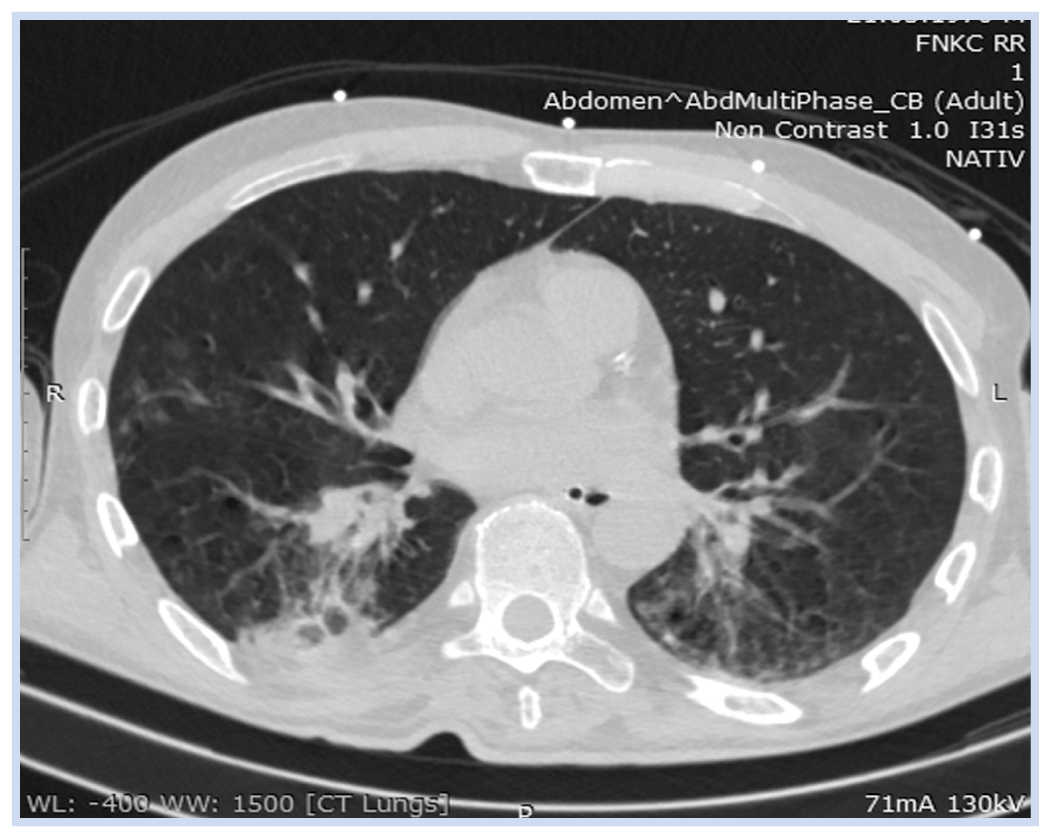

По результатам компьютерной томографии (КТ) при поступлении у пациента выявлены признаки двусторонней нижнедолевой пневмонии (рис. 1), значительная лейкоцитурия (табл. 1). Пациенту была назначена антибактериальная терапия с положительным эффектом (табл. 1–3).

Рис. 1. Пациент К., 50 лет, с посттравматической гидроцефалией и посттрепанационным дефектом костей свода черепа при поступлении: компьютерная томограмма от 30.03.2020

Примечание. Визуализируется двусторонняя нижнедолевая пневмония.